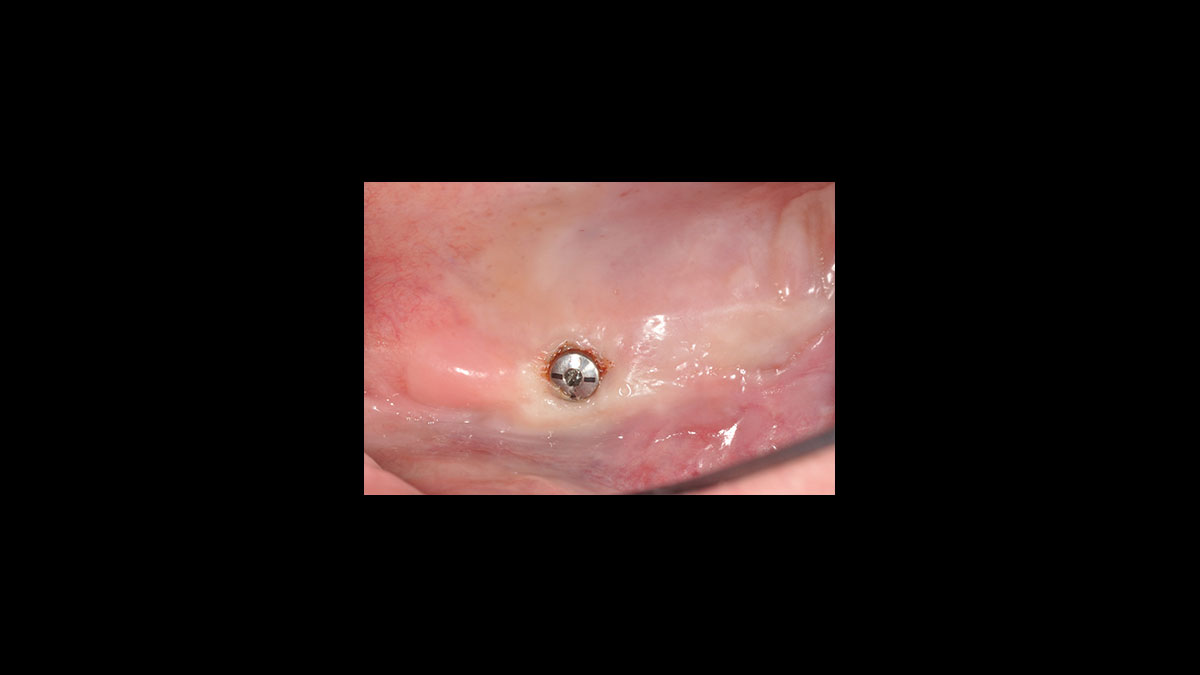

Descubrimiento del implante